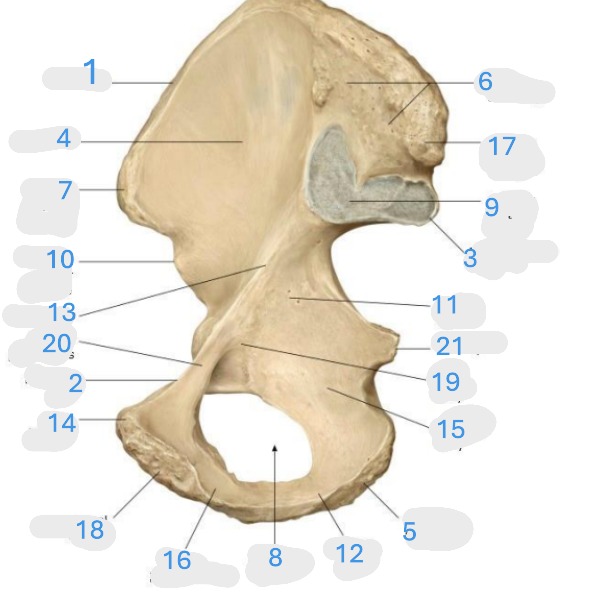

Where is the iliac crest

1

Where is the pectineal line

2

Where is the posterior iliac spine

3

Where is the iliac fossa

4

Where is the ischial tuberosity

5

Where is the iliac tuberosity

6

Where is the anterior superior iliac spine

7

Where is the obturator foramen

8

Where is the auricular surface of the ilium

9

Where is the anterior inferior iliac spine

10

Where is the ilium body

11

Where is the ischial ramus

12

Where is the arcuate line

13

Where is the pubic tubercle

14

Where is the ischium body

15

Where is the inferior pubic ramus

16

Posterior superior iliac spine

17

Where is the symphyseal surface

18

Where is the pubis body

19

Where is the superior pubic ramus

20

Where is the ischium body

21